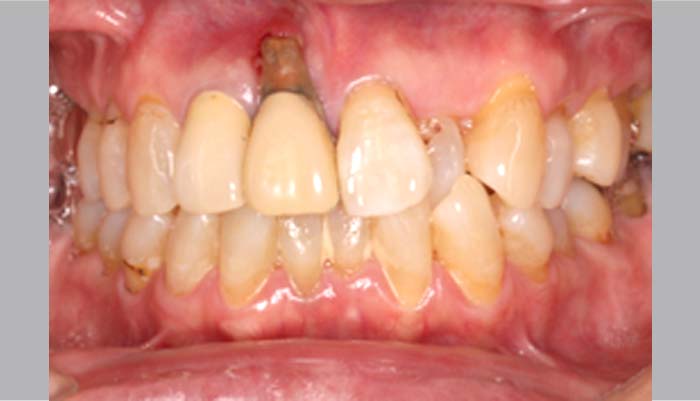

症例紹介

歯周病で多くの歯を失ってしまった方や、

歯周病が原因で抜歯を勧められている方、

歯周病の専門家に相談してみたいという方も、

ぜひ当院にお任せください。